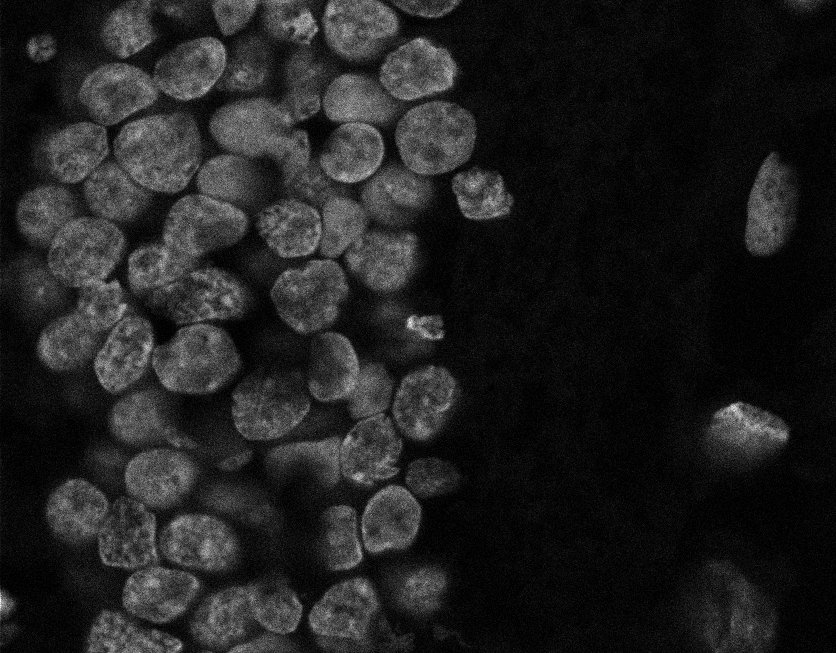

Nuclei